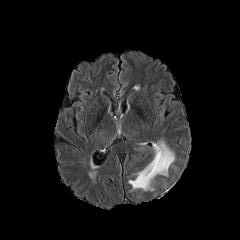

We observe that the generated normal-looking from ANT-GAN can also be used to directly segment the image, since the only difference between a synthesized normal-looking image and its real abnormal counterpart is region with the lesion. To illustrate this, we calculate the absolute difference between x𝑥x and 𝒢A2N(x)subscript𝒢A2N𝑥\mathcal{G}_{\rm{A2N}}(x) and show the segmentation after binary thresholding at 0.1 in Figure 9.

Refer to caption

(a) Tumor x𝑥x

(b) 𝒢A2N(x)subscript𝒢A2N𝑥\mathcal{G}_{\rm{A2N}}(x)

(c) Prediction

(d) Label

Figure 9: Example segmentation obtained by taking the absolute difference between the real tumor MRI x𝑥x and the generated normal-looking MRI 𝒢A2N(x)subscript𝒢A2N𝑥\mathcal{G}_{\rm{A2N}}(x), after binarization at a preset threshold.